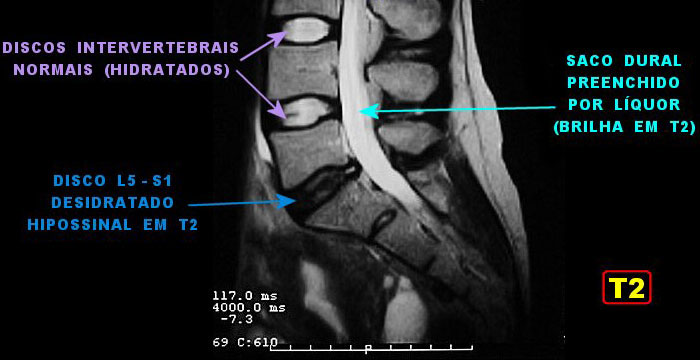

Podemos ver o disco desidratado entre a 5ª vértebra lombar e a 1ª sacral, em um exame de ressonância nuclear magnética (RNM).